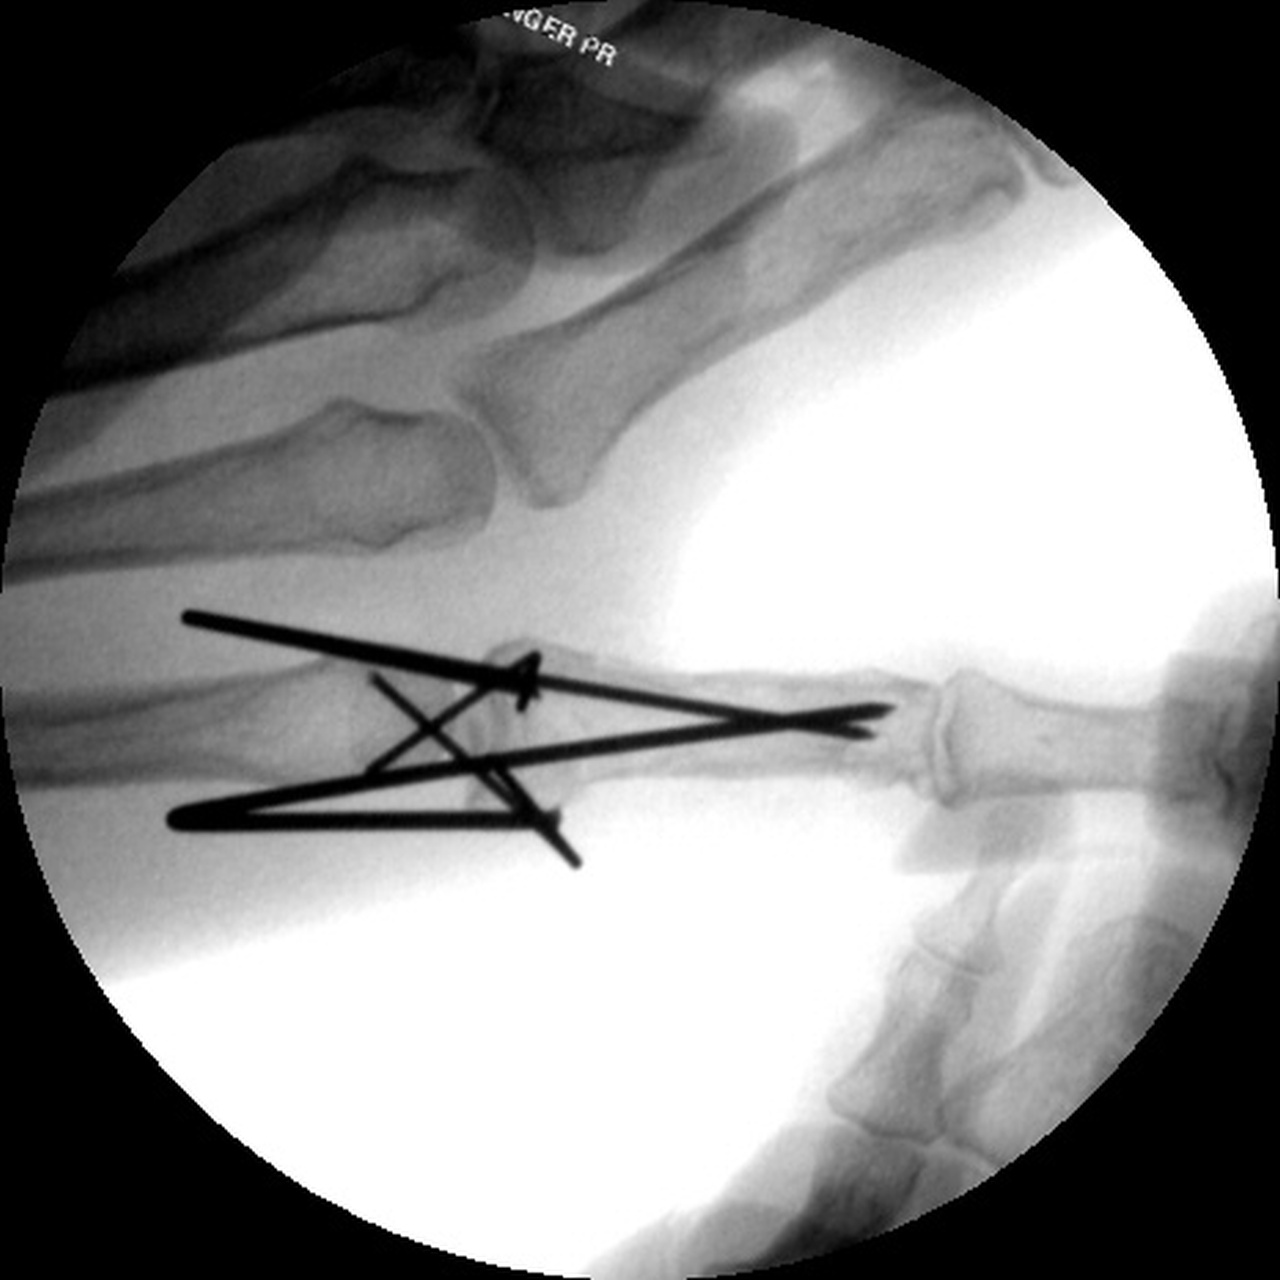

| Closed reduction and insertion of interfragmentary and proximal fracture fragment pins. |

| Pins were bent to

overlap and then bonded with heated thermoplastic

splint material. |